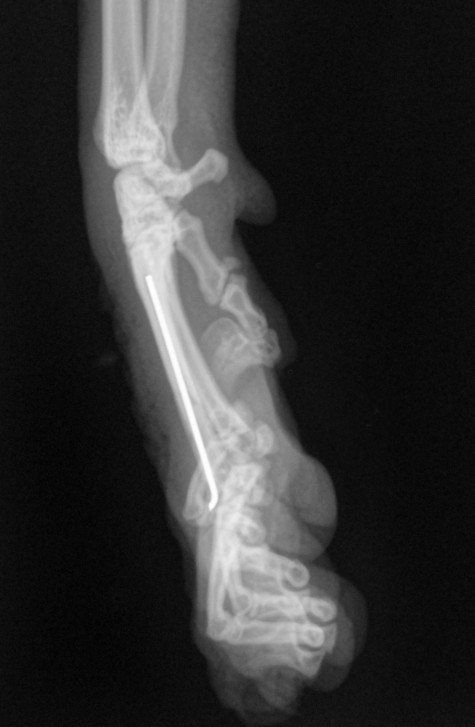

Il a eu le bon réflexe de la déposer chez le vétérinaire du quartier qui a constaté que la petite avait sa patte avant gauche déformée. Il s’est avéré, en grandissant, qu’elle ne se sert pas de sa patte.

Nous l’avons emmené en consultation au CHVA de Beaulieu à Nantes pour avoir l'avis d'un spécialiste. Hélas, il faudra l’amputer car Uanna n’a aucune sensibilité à cette patte. Elle est handicapée et cela devient un fardeau pour elle car Uanna a du mal à se déplacer. Elle s’est blessée plusieurs fois, cela devient urgent pour elle

Coût de l’opération : 1064,20€ (devis en photo)